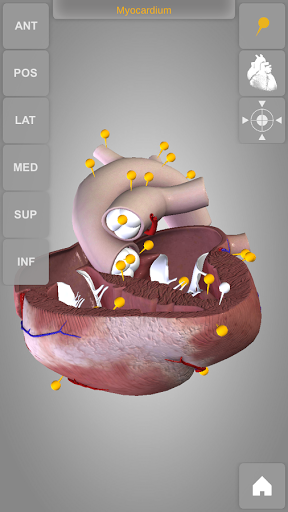

Heart 3D Atlas of Anatomy allows you to rotate a highly realistic 3D heart model as it was in your hands.

The human heart anatomical 3D model is revolvable in any direction giving a 360° view of the object.

User can choose external view or section view. Moreover, the names of specific anatomical areas can be shown touching the related pins (available in the full version only).

Heart app is part of 3D Atlas of Anatomy collection, a human anatomy reference atlas for tablet and smartphone devices. The 3D medical models in these apps are similar to classic real plastic models but with the great benefits to be always available on your portable devices when you need them and occupy no physical space.

These apps can be of great help for students of medicine or to anyone who needs to study human anatomy shape in detail and from any angle. Immediacy and simplicity together with high quality are distinctive features of the app.